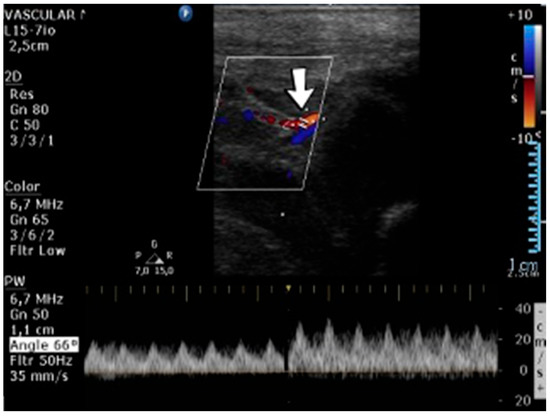

A 10-day-old female neonate (36 weeks, 2.37 kg), known before birth with Dandy–Walker Syndrome, presented with hydrocephalus and severe coarctation of the aorta. Two central arterial lines were placed—in the right brachial and the left femoral arteries—and the aortic defect was corrected. One day later, hematoma of the right arm and ecchymosis near the insertion site of the brachial arterial catheter were noticed. Vascular ultrasound could not reveal any blood flow on the axillary or the proximal brachial arteries, leading to the removal of the central arterial catheter (Figure 14). Continuous heparin infusion was initiated, followed by treatment with enoxaparin. Later, blood flow was reestablished on both axillary and brachial arteries.

Figure 14.

No blood flow on the axillary or the proximal brachial arteries on vascular ultrasound.

Genetic testing confirmed inherited thrombophilia, with a positive MTHFR C677T homozygous gene mutation and Antithrombin, Protein S, and Protein C deficiencies. Normal PAI-1 levels were detected. There was a positive family history of maternal thrombophilia (MTHFR A1298C, MTHFR C677T, PAI-1 4G/5G promoter, and Factor XIII (Val34Leu) heterozygous gene mutations and Protein S deficiency), treated with enoxaparin and acetylsalicylic acid during pregnancy. There were no maternal miscarriages.